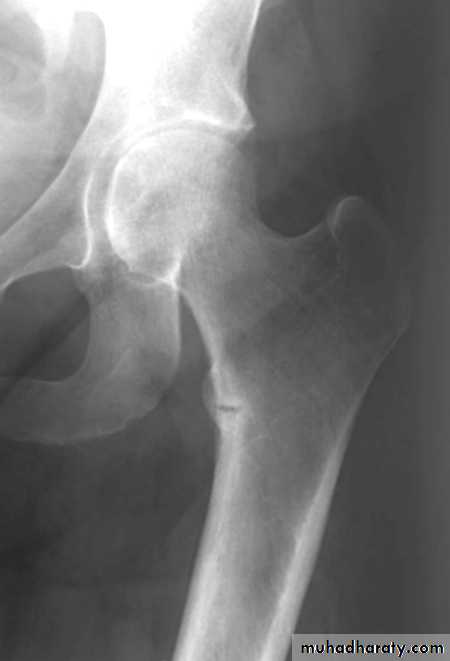

hyperparathyroidism

Excessive secretion of PTH.May be primary , secondary, or tertiary.

PTH- enhance calcium conservation resulting in hypercalcaemia and hypercalciuria and

Hyperphosphouria.Bone resorption manifest by ostitis fibrosa cystica and subperiosteal resorption.

3- bone pain and pathological fractures.